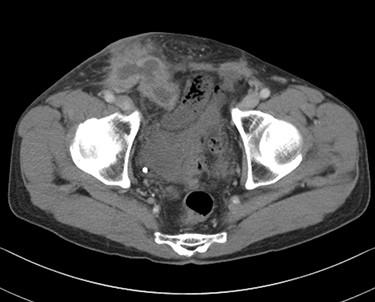

Eleven years after hernia repair, the patient presented with redness, pain and swelling in the right inguinal region (Fig. 3). Laboratory studies revealed mild elevation of inflammatory markers (white blood cell count 13 000 /μl, C-reactive protein 2.8 mg/dl). Physical examination showed mild tenderness at the area of erythema. CT scan revealed abscess formation with contrast effect in the right inguinal region (Fig. 4). The patient was diagnosed with a mesh infection and abscess formation. Emergency operation was performed. The abscess cavity was opened and granulation tissue and the mesh-plug removed (Fig. 5). The aponeurosis of the external oblique muscle was repaired, with no reconstruction of the posterior wall. A closed drain was inserted subcutaneously at the time of wound closure. Abscess culture was positive for Enterobacter cloacae. He did well postoperatively except for a surgical site infection, discharged on postoperative Day 14. The patient remains free of recurrence of inguinal hernia after 3 years of follow-up.

Computed tomography scan revealed abscess formation with contrast effect in the right inguinal area.